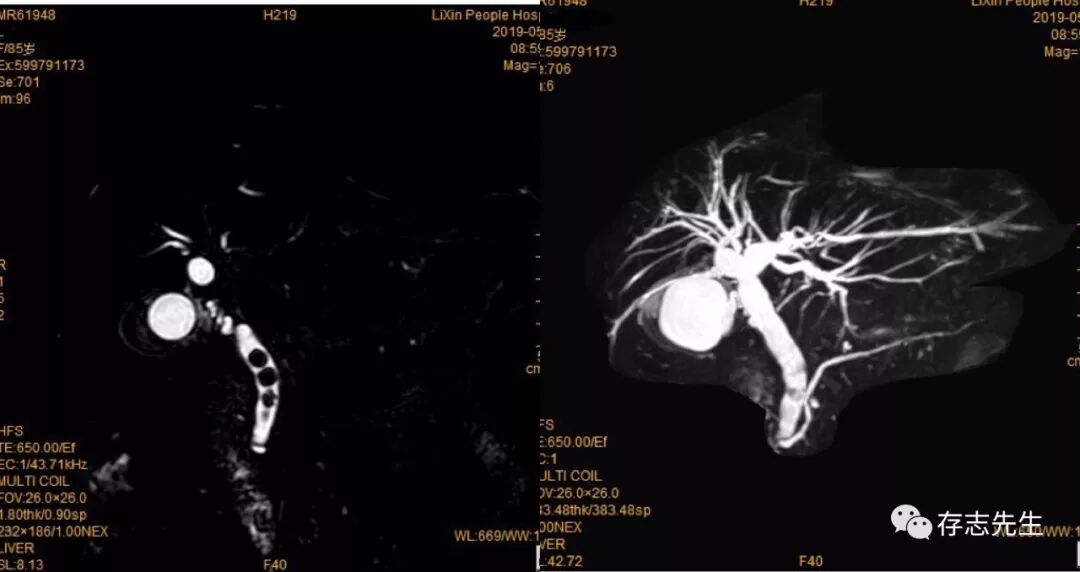

胆囊不充盈胆道无扩张

MRCP一直都是困扰我们1.5T老机型核磁的问题!图像质量不稳定时好时坏,有时扫描时间浪费了很长,也没有得到较好的图像!MRCP图像质量和患者本身因素息息相关,如肝内胆管无扩张,胆囊不充盈、呼吸紊乱、胸水腹水、胃肠道液体等,都会引起图像的清晰度,所以MRCP对被检者有较高的要求。